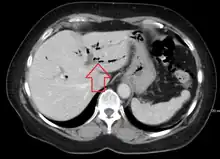

CT scan of pneumobilia

Pneumobilia is the presence of gas in the biliary system. It is typically detected by ultrasound or a radiographic imaging exam, such as CT, or MRI. It is a common finding in patients that have recently undergone biliary surgery or endoscopic biliary procedure. While the presence of air within biliary system is not harmful, this finding may alternatively suggest a pathological process, such as a biliary-enteric anastomosis, an infection of the biliary system, an incompetent sphincter of Oddi, or spontaneous biliary-enteric fistula.